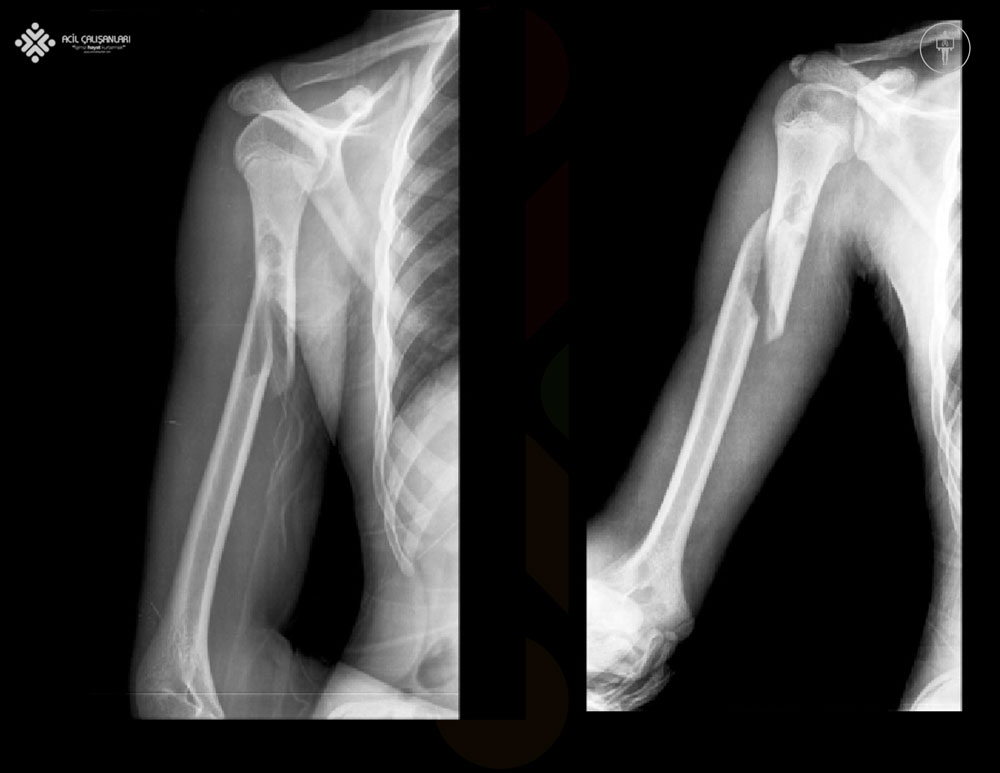

20 yaşında bir erkek hasta, futbol oynarken üst ekstremitesinde meydana gelen bir yaralanma nedeniyle acil servise başvuruyor. Gelmeden önce çok ağrısı olduğu için ağrı kesici aldığını belirtiyor. Hasta acil hekimi tarafından değerlendirildiğinde sağ önkol ve elin lateral tarafında uyuşukluk olduğu saptanıyor. Hastaya hemen aşağıda görüldüğü gibi sağ humerus grafisi isteniyor. Bu tür bir yaralanmada aşağıdaki klinik bulgulardan hangisinin görülmesi beklenir?

Humerus kırığı olan hastalarda radial sinir yaralanabilir çünkü radial sinir kemiğin lateral sınırındaki radial oluktan geçer. Bu tür bir yaralanmada, hastada bilek ekstansiyonunda zayıflık ve parmaklarını uzatamama görülür. Radial sinirdeki bir lezyon dirsek ekleminin yukarısında olduğunda, hasta radial sinirin dermatomu boyunca önkol ve elde uyuşukluktan da şikayet edebilir. Bilgisayarlı Tomografi (BT), MR kadar hassas olmasa da, acil durumlarda sıklıkla daha önce yapılır ve tarama yöntemi olarak kullanılır. Kontrastlı çekilen beyin tomografisinde görüntüleme bulguları lezyonun evresine bağlıdır. Erken serebrit genellikle düzensiz, düşük yoğunluklu bir alan olarak ortaya çıkar ve bu alan artmaz ya da seyrek olarak yamalı bir şekilde artabilir. Serebrit ilerledikçe, daha belirgin, kenarları genişleyen bir lezyon görünür hale gelir. Geç apsesi olan hastalarda seri BT incelemeleri giderek azalan ödem ve kitle etkisi gösterir. Beyin apsesi duvarı genellikle pürüzsüz ve düzenlidir, 1 mm ila 3 mm kalınlığındadır ve parankimal ödem ile çevrilidir.